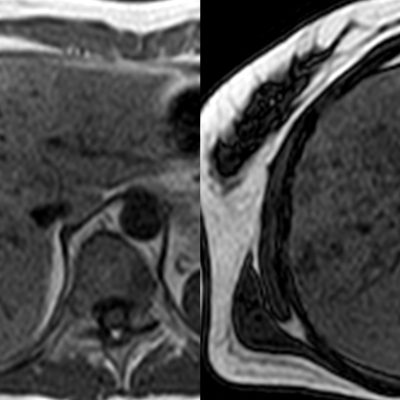

El estudio se complemento con resonancia magnética, donde se demostró la presencia de múltiples imágenes focales hepáticas confluentes con disminución de la señal en secuencias fuera de fase, no mostrando alteración de la señal en secuencias potenciadas en T2, sin signos de restricción al pulso difusión ni refuerzos anómalos luego de la administración de contraste endovenoso, estos hallazgos confirman la sospecha de esteatosis focal multinodular (fig. 5, 6 y 7).